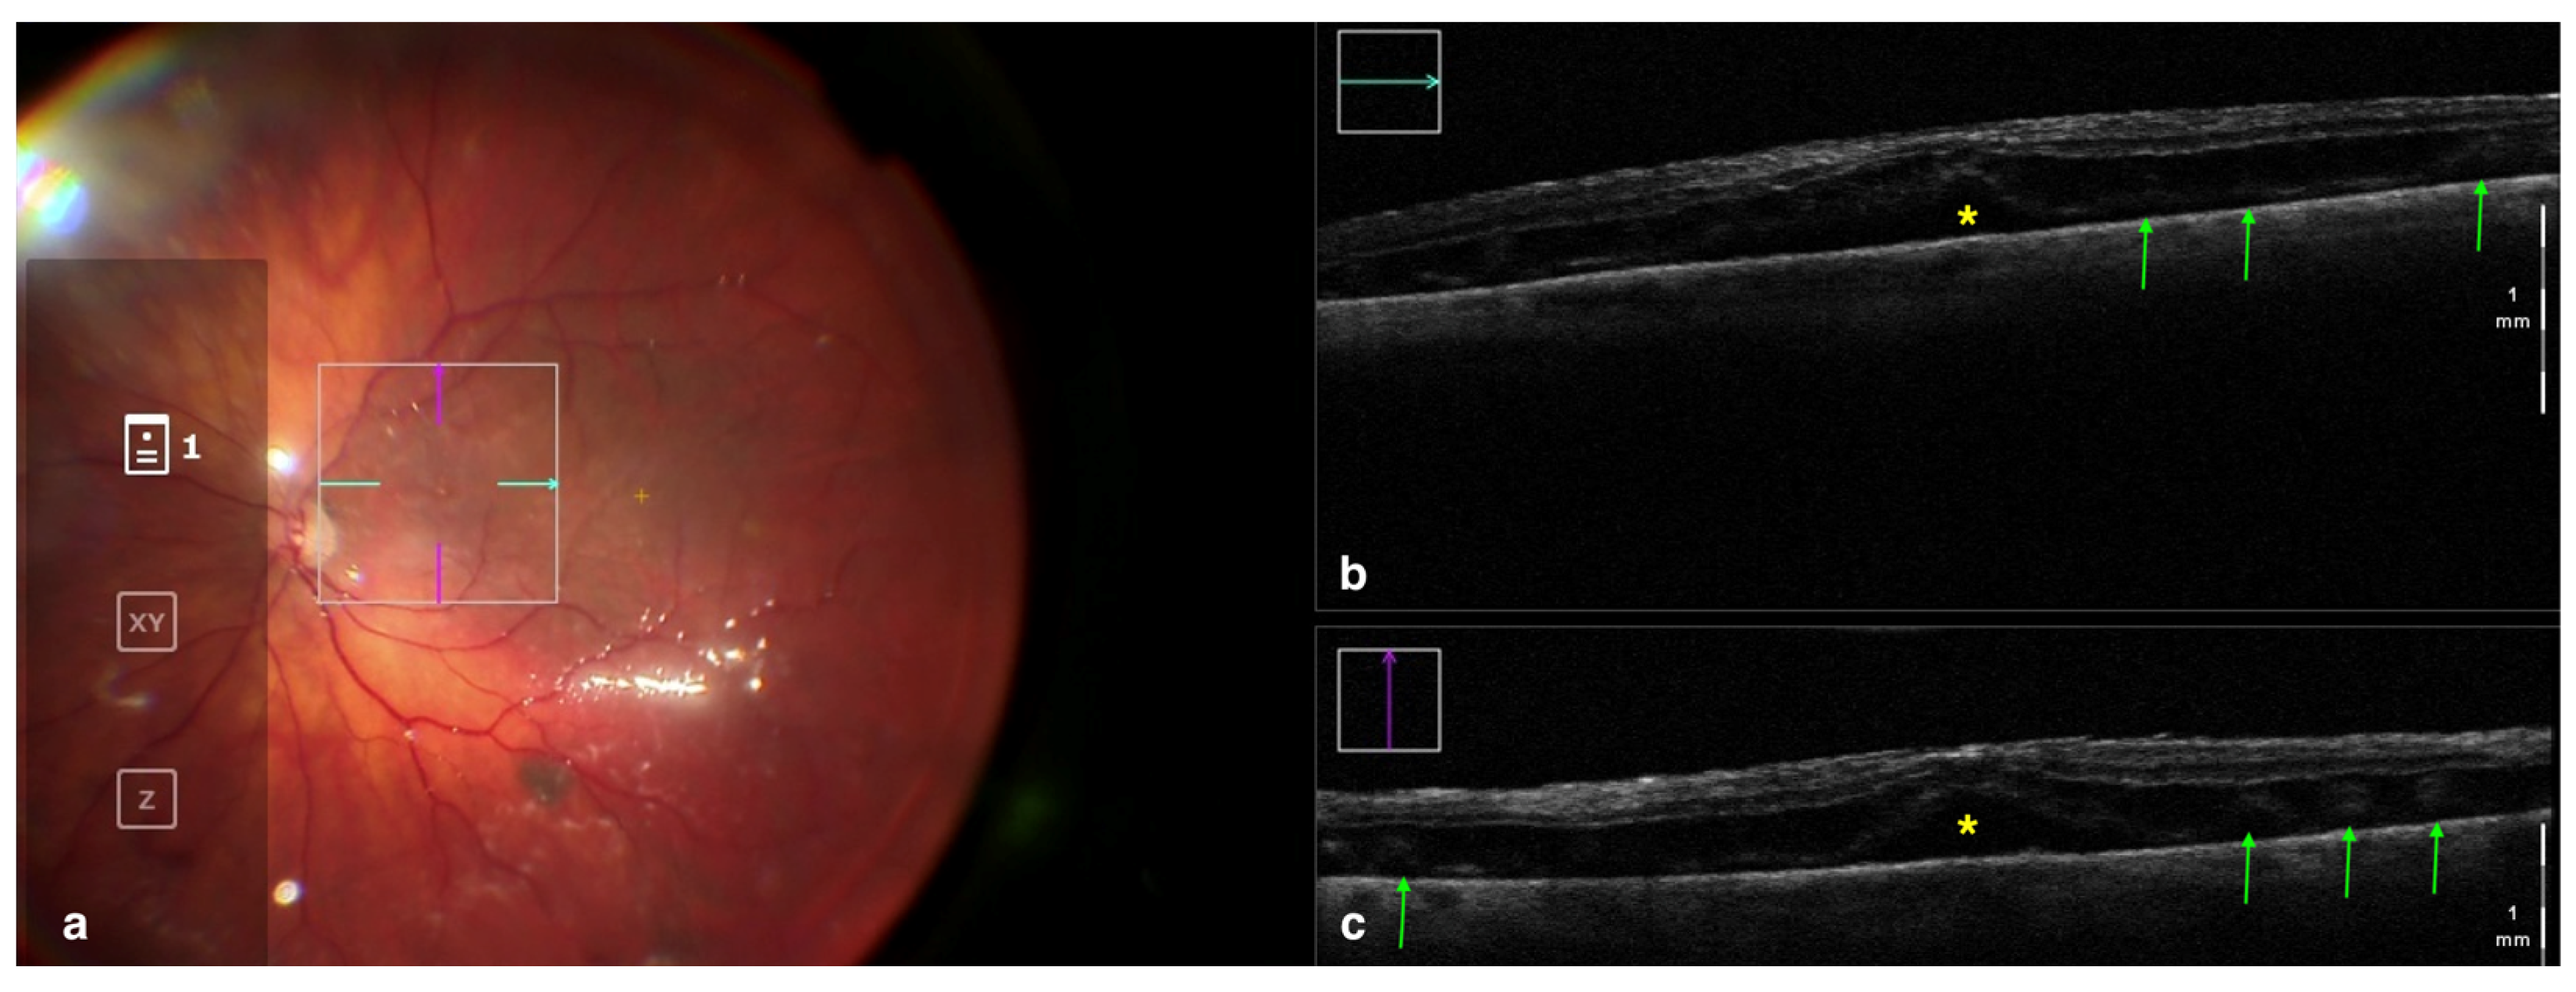

- Nishitsuka, K.; Nishi, K.; Namba, H.; Kaneko, Y.; Yamashita, H. Peripheral Cystoid Degeneration Finding Using Intraoperative Optical Coherence Tomography in Rhegmatogenous Retinal Detachment. Clin. Ophthalmol. 2021, 15, 1183–1187. [Google Scholar] [CrossRef]